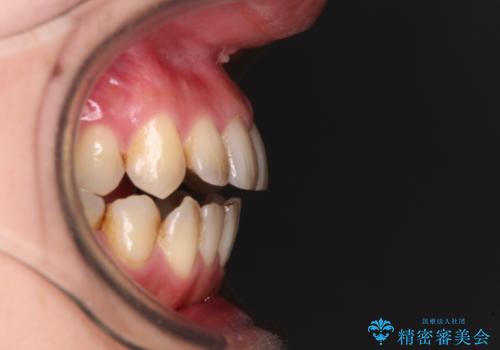

- 上下前歯の隙間を気にして来院された患者様です。

下顎前歯が1本欠損しており、上下小臼歯はクロスバイトとなり、上下前歯の接触もないという不正咬合の状態でした。

クロスバイトはワイヤー矯正が得意とするところであり、上下前歯の非接触や開咬はインビザラインの得意とするところであるので、ワイヤー装置により事前にクロスバイトを改善し、その後にインビザラインにて仕上げていくこととしました。